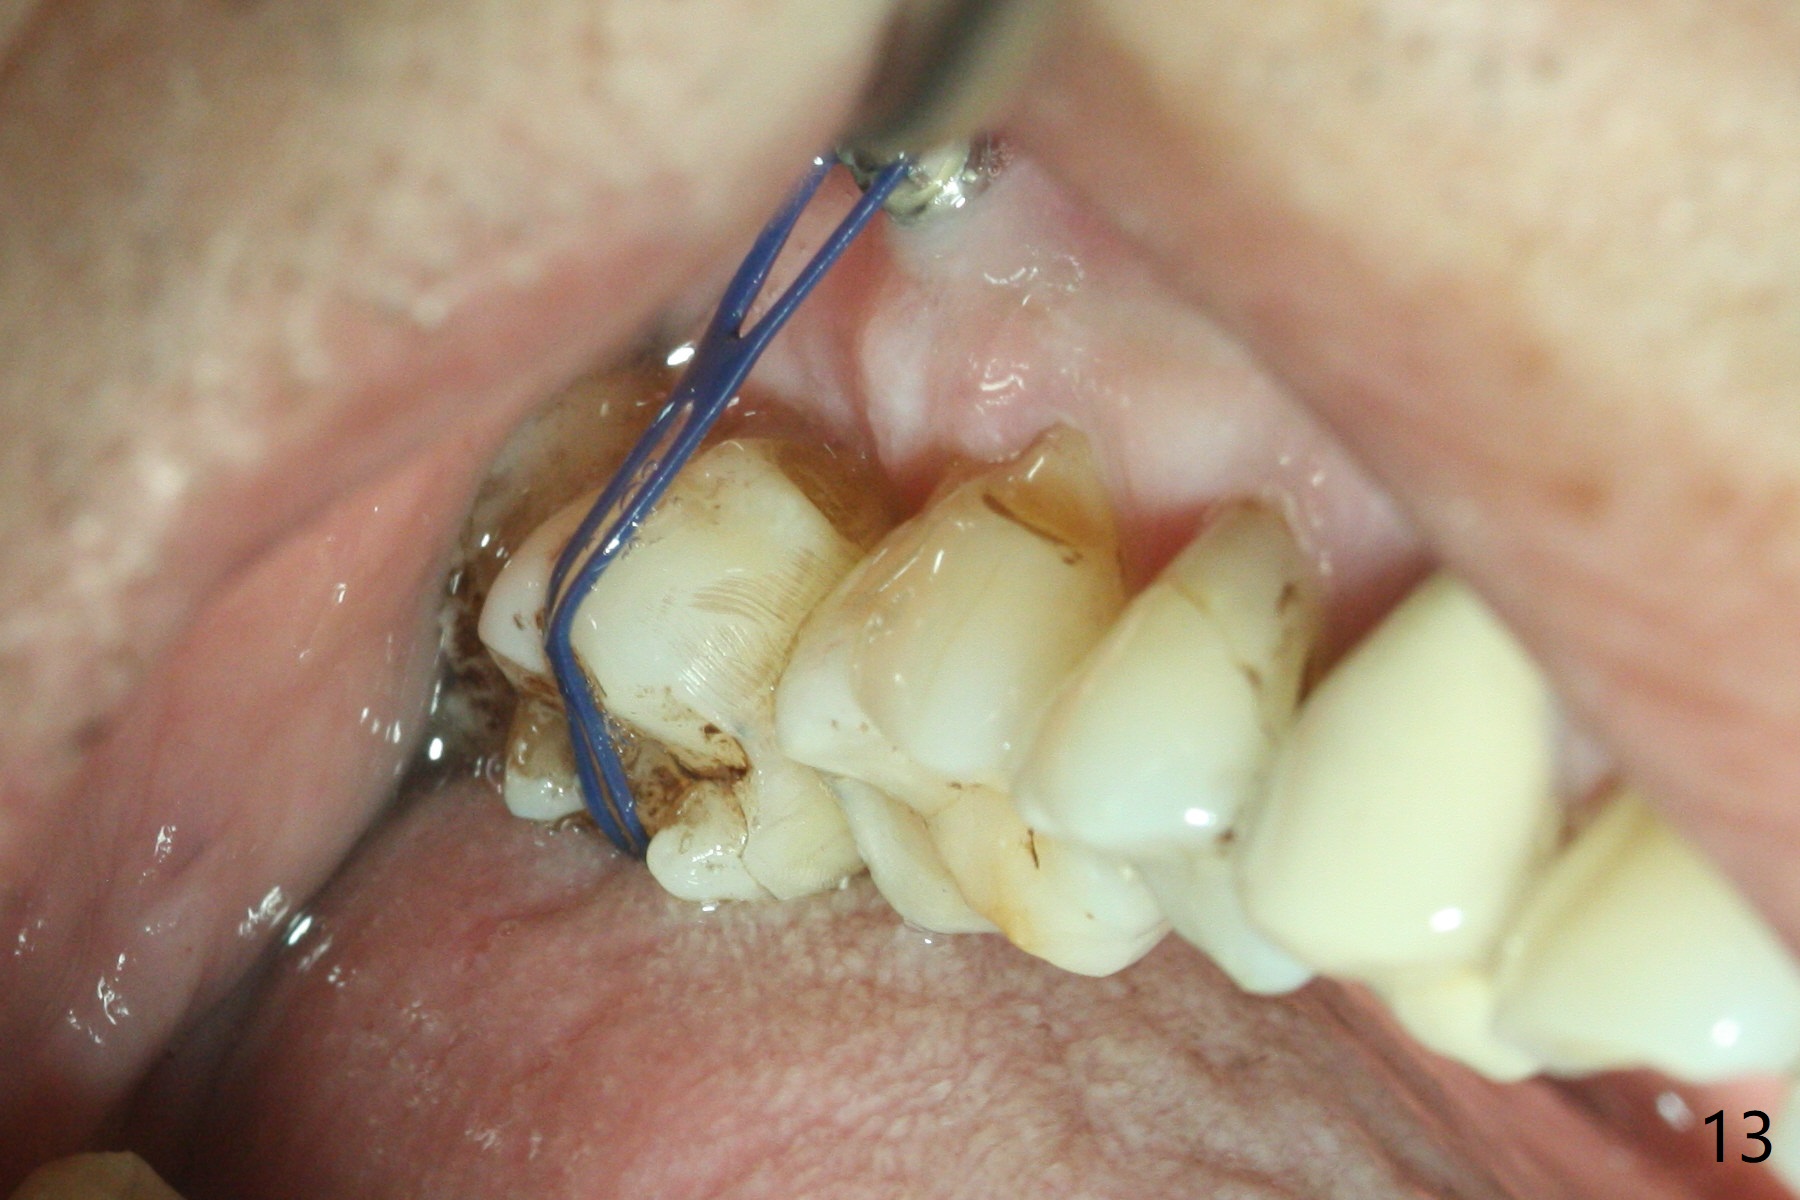

Two days post #31 implant placement, the patient returns for orthodontic intrusion of the tooth #2 with mini-implants (Fig.1). The palatal cusps have been trimmed (Fig.2 ^), since they almost contact a healing abutment at #31(*, Fig.3). Two mini-implants are to be placed mesiobuccal and distopalatal to the affected tooth. After minimal injection of Lidocaine, a 1.6x6 mm Tomas implant is placed in full length mesially (Fig.4), while the other (1.6x8 mm) half way (Fig.4). Following change in implant site mesially (Fig.6 >), the implant is half inserted (Fig.5). It appears that the tip of the distal implant is toward the tooth #1 (Fig.5). After withdrawing the implant partially, it is re-directed to apparently ideal trajectory (Fig.7). Ideally the mesial implant (Fig.8) should have been placed partially initially (Fig.4,5,7) so that the trajectory could have been able to be changed.

The buccal implant becomes loose in 2-3 months. When the wound heals (Fig.9 <), a 1.6x`10 mm implant is placed with the help of PAs for trajectory (Fig.10,11) and in the nonkeratinized gingiva (higher, the crestal bone may have been traumatized by previous implant placement, Fig.12). Two months later, the tooth #2 is partially intruded (Fig.13). A provisional (Fig.14 P) is fabricated in the osteointegrated implant at #31 with supraocclusion so that the remaining dentition has no occlusal contact (*). The periodontally compromised tooth #2 becomes in buccoversion in 2 months. The provisional is removed, while a lingual button is placed in the buccal surface of the tooth #2 (Fig.15). With power chain attached to the lingual mini-implant, the tooth #2 is lingualized in 2 months. The provisional and the implants are reused for final intrusion (Fig.16). The treatment is nearly 11 months. The buccal implant, although placed in the movable mucosa, remains stable and healthy (Fig.17). The tooth #1, as a guiding plane (to prevent #2 from distalization during intrusion), is not extracted after intrusion is completed.